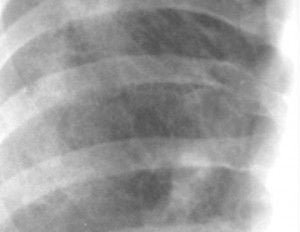

Ground Glass

Similar como veíamos al patrón reticular fino. Es difícil de reconocer en radiografía simple y muy característico en los estudios de TAC.

Puede describirse como un aumento ténue de la densidad, no ocultando la vasculatura pulmonar (lo que es más evidente en las bases) pero con escasa definición de los márgenes de los vasos en la radiografía simple, a veces constituyendo el único argumento de base para incluirlo en el conjunto de enfermedades difusas. Cuando la lesión se extiende o es más profusa en un área determinada puede causar un aspecto “granular”.

Aspecto en “vidrio deslustrado” (“granular”)